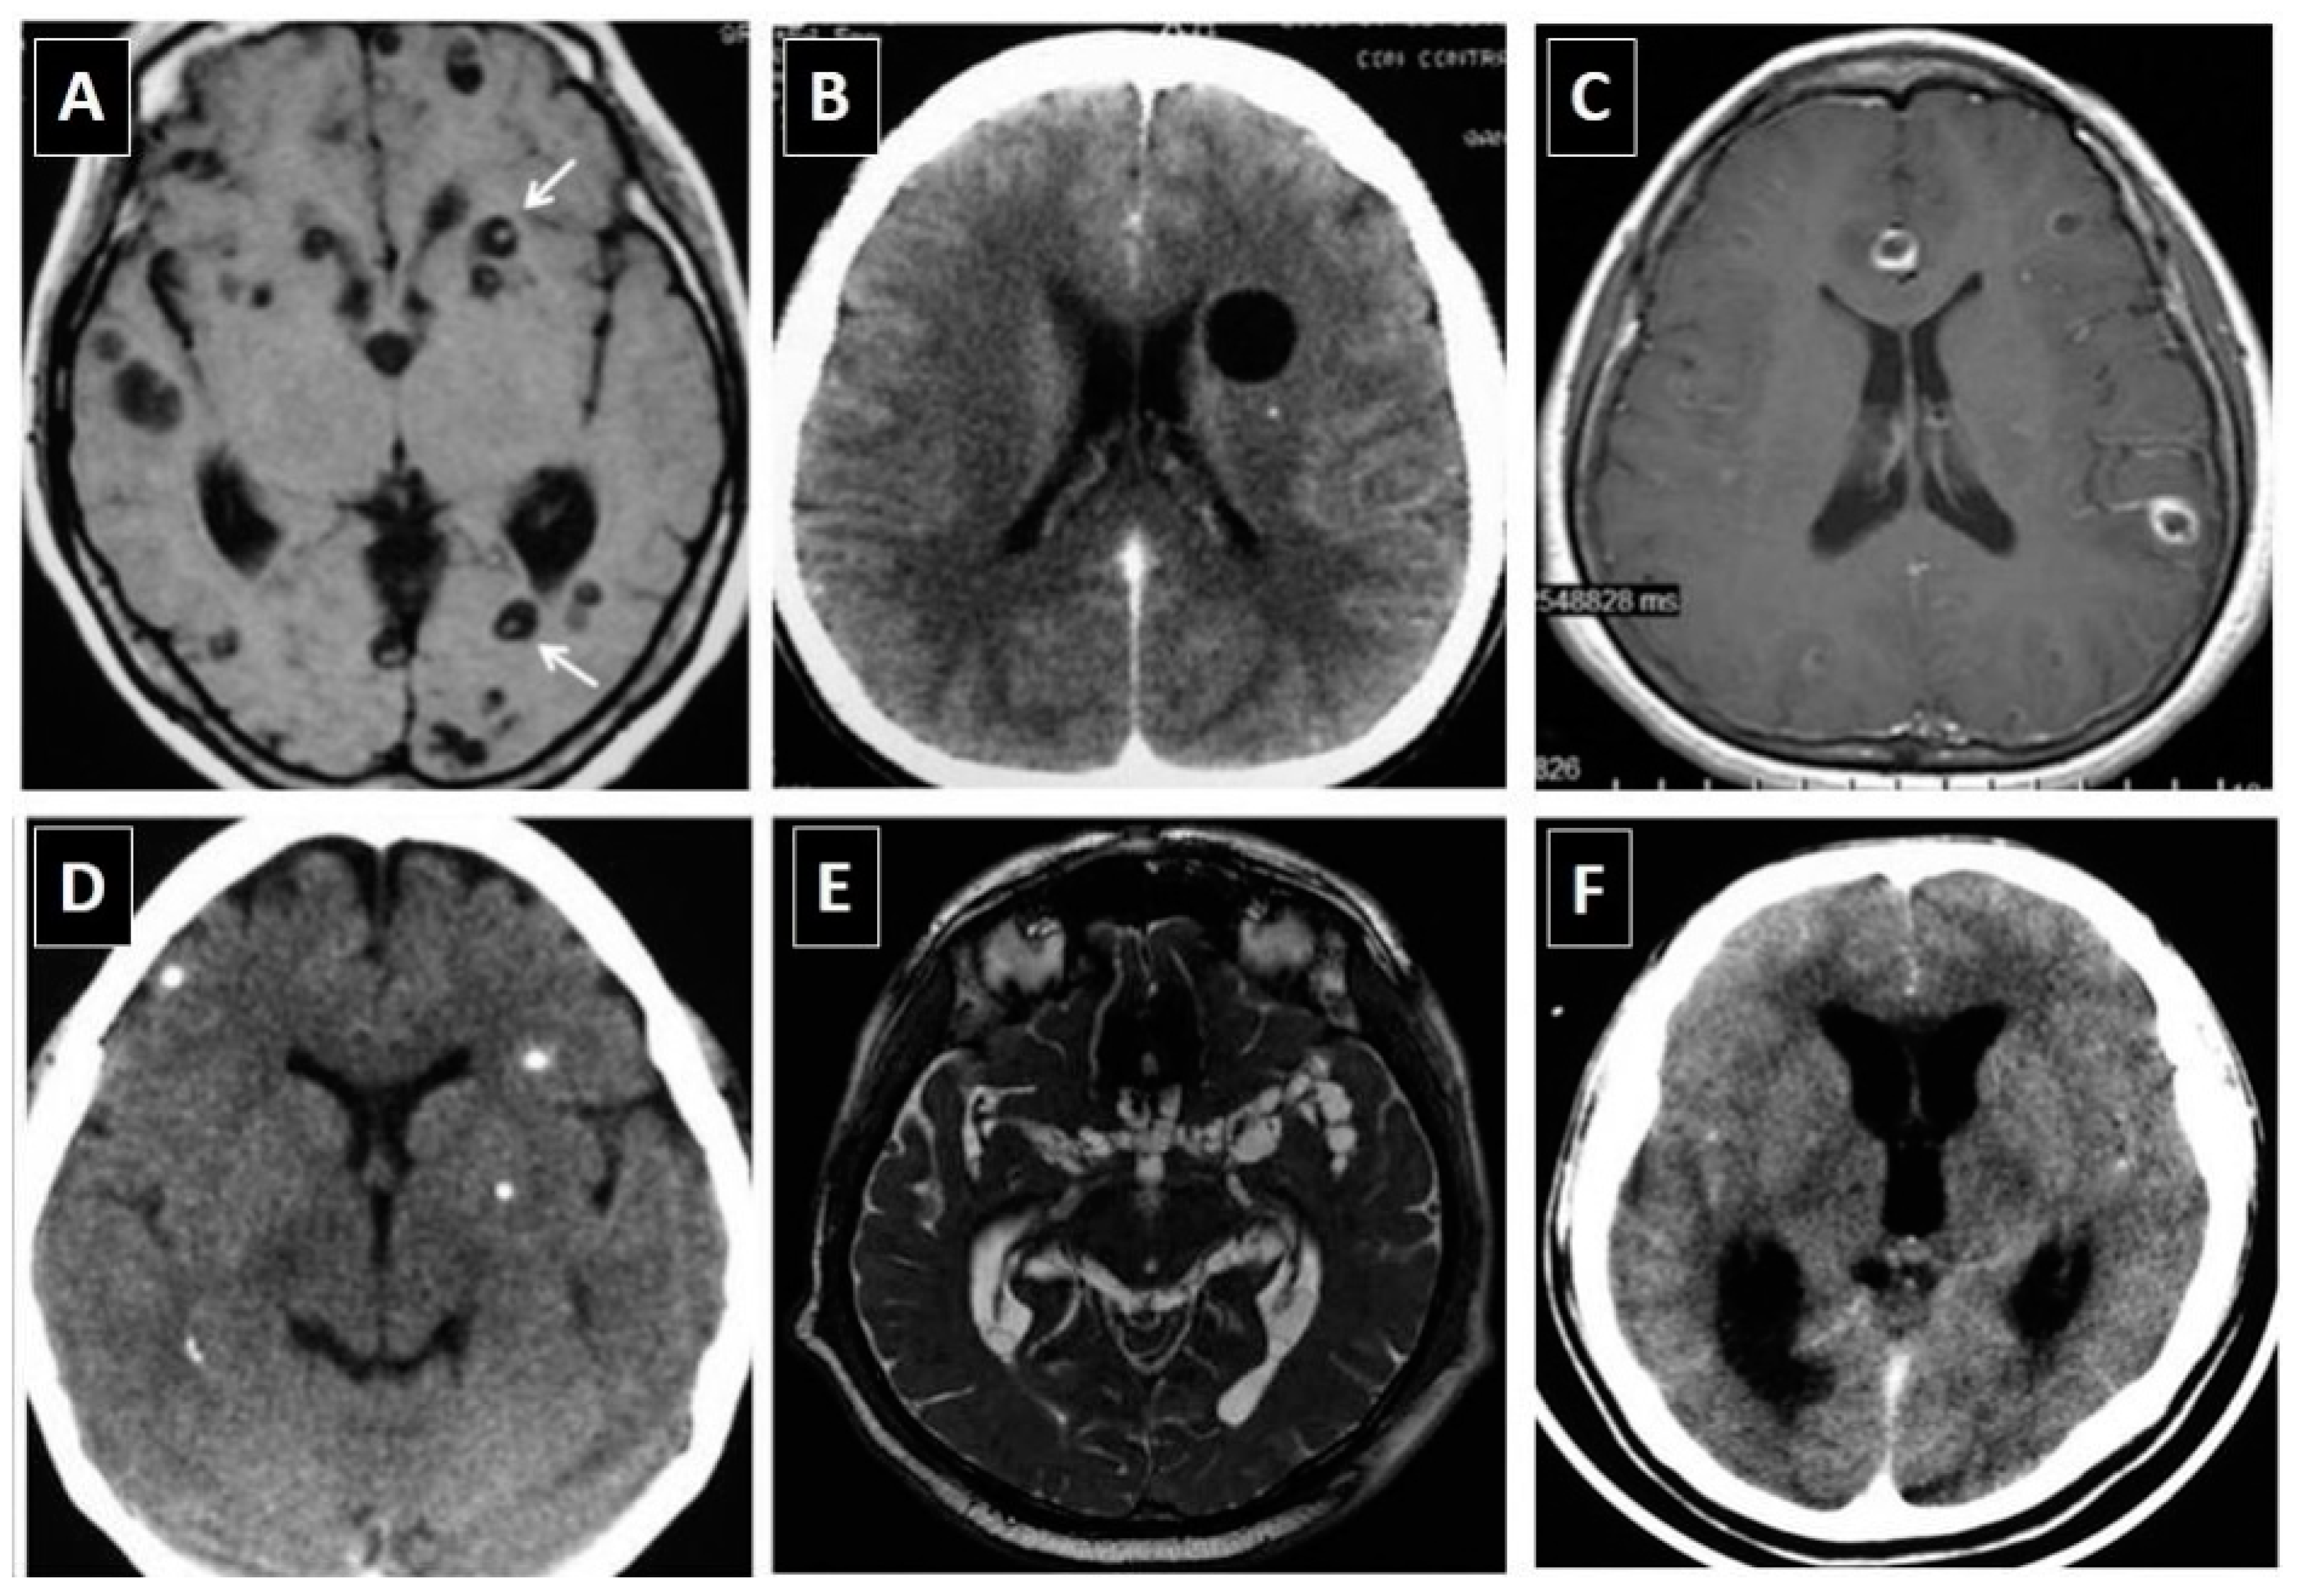

* **Neurocysticercosis** (*Taenia solium* larvae):

- Stages: Vesicular (scolex visible, pathognomonic), colloidal vesicular, granular nodular, calcified nodular.

- Imaging: CT/MRI shows cysts; "hole-with-dot" sign.

> * **Neurocysticercosis** (*T. solium*): **Ring-enhancing lesions with scolex**.